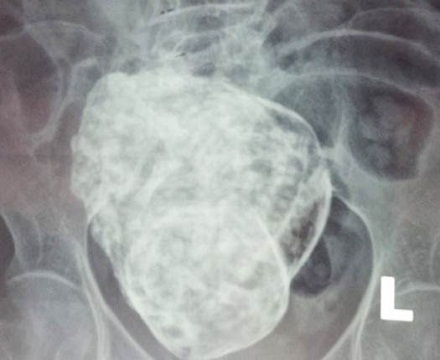

Qua thăm khám và chụp X-quang, các bác sĩ phát hiệncó hình hài bào thai nằm trong ổ bụng của cụ bà. Các bác sỹ dự đoán thai nhi trong bụng bà Sáu đã có gần 30 năm vì bệnh nhân mãn kinh cách đây 27 năm.

Kết quả chụp MRI cho thấy có khối bất thường trong ổ bụng vùng hạ vị, ở sau bàng quang, có hình dạng giống thai nhi, khả năng thai vôi hóa.Các bác sỹ nhận định đây là trường hợp thai trong ổ bụng chết lưu đã rất lâu, hóa thạch (lithopedion) và hiện đang có biến chứng gây đau dữ dội vùng hạ vị và thắt lưng, có thể sẽ cần đến phẫu thuật để loại bỏ khối thai này.